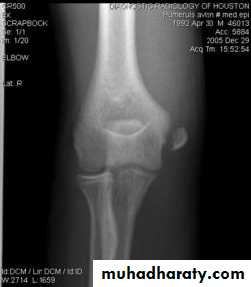

Fracture medial epicondyle of the humerus

It is occur due to fall on out stretched hands ; the medial epicondyl is avulsed by the effect of the strong flexor muscles of the wrist . If the elbow joint is dislocated or subluxated even momentarily , the fracture piece may introduced into the joint .

Clinically :

History of trauma , pain and tenderness , swelling , sensation and power of the fingers should be tested to exclude ulnar nerve damage .

Treatment :

Minor displacement less than 5 mm. need only back slab in elbow flexed , after 7 days do full p.o.p. for 2-3 weeks .If the piece is trapped into the joint , then it must be freed either by manipulation under anesthesia , if failed or the piece is severely displaced then we should do open reduction and fixation by K wire or screw .

Complication : early : ulnar nerve damage .